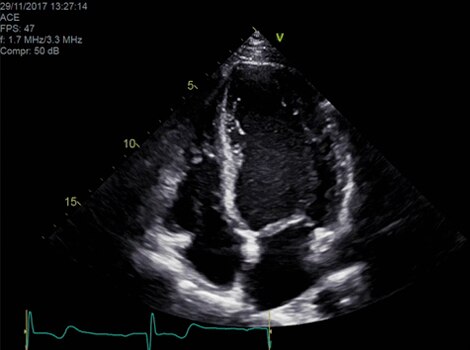

Vivid Portfolio

Cardiac Auto Doppler automatically provides Doppler measurement results for the most common parameters, with minimal user guidance.  Read More

Vivid E95

cSound™ beamforming technology for exceptional visualization quality with impressive resolution in 2D, color flow, Doppler and 4D formats. Read More

VividTM Family Cardiac Ultrasound Automated Function Imaging (AFI)

Assess left ventricular function and cardiac performance with clarity, improving clinical confidence. Read More

Vivid Family Cardiac Ultrasound

Vivid E95 with cSound performance makes 4D as easy as 2D to quantify left ventricular wall motion. Read More